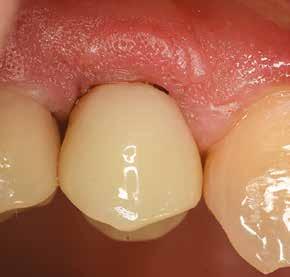

1. ábra: Műtét előtti fogászati panorámafelvétel, amelyen a hiányzó felső állcsont jobb első premolárisát és a szabad véggel rendelkező hidat láthatjuk. — 2. ábra: Az implantátum méreteinek megtervezése CBCT-vel. 3. ábra: Bukkális lágyrészdefektus. — 4. ábra: A biológiai szélesség értékelése a vertikális lágyszövetvastagság alapján. 5. ábra: Palatinális „tekercslebeny” – Palatal roll flap. — 6. ábra: Bredent medical copaSKY 4x10 implantátumbeültetés. 7. ábra: Szubkresztális implantátumbeültetés a várható biológiai szélességnek megfelelően.

8. ábra: Egyéni ínyformázó titánbázison, tulipán alakú emergenciaprofillal. — 9. a. ábra: A sebzárás okkluzális nézete.

(2. ábra). A lágyszövetek értékelése Seibert szerinti I. osztályú csontdefektust állapított meg (3. ábra), ezért a beavatkozáskor palatinális „tekercslebenyt” preparáltunk (palatal roll flap), és implantációt végeztünk, hogy kompenzálni tudjuk a bukkális lágyszövet-behúzódást. Megmértük a vertikális lágyszövetvastagságot, és úgy terveztük, hogy a szubkresztális implantátum beültetése összhangban legyen a biológiai szélesség kialakulásával a transzgingivális gyógyulási periódus alatt (4. ábra)

Az eljárást helyi érzéstelenítés mellett végeztük (4%-os articaine-hidroklorid 1:100 000 adrenalinnal). Papillakímélő, U alakú palatális bemetszést végeztünk, teljes vastagságú nyálkahártyalebeny preparálás történt, a lebenyt bukkálisan feltekertük (5. ábra). A lebeny bukkálisan feltekert részén de-epitelizációt végeztük el, amellyel kompenzálni tudtuk a bukkális lágyszöveti defektust. Szakaszos előfúrást végeztünk, és a bredent copaSKY 4x10 implantátumot 30 Ncm behajtási nyomatékkal helyeztük be (6. ábra). Az implantátumot 1 mm-re szubkresztálisan helyeztük be, hogy később szélesebb emergenciaprofilt tudjunk kialakítani (7. ábra). Az egyedi ínyformázó úgy készült, hogy kompozitot vittünk fel a titánbázisra, és így formáztuk a lágyszöveteket a transzgingivális gyógyulási fázis során (8. ábra). Az egyéni ínyformázó tulipán formájú, hogy kialakítsa a kívánt emergenciaprofilt. A lágyszövetet feszülésmentesen zártuk #6/0 nem felszívódó, monofil fonallal (Optilene, B. Braun Deutschland; 9. a–b. ábra). Posztoperatív röntgenfelvétel készült, ami alapján az implantátum a szomszédos fogakkal párhuzamos elhelyezést mutatott (10. ábra). Posztoperatív utasításokat adtunk a páciensnek a műtéti terület körüli szájhigiénia fenntartása érdekében. A beavatkozást követő egy héttel a varratokat eltávolítottuk, és a kezelt terület kielégítő gyógyulást mutatott (11. ábra). A 4 hónap utáni késleltetett terhelést a páciens kívánsága szerint terveztük.